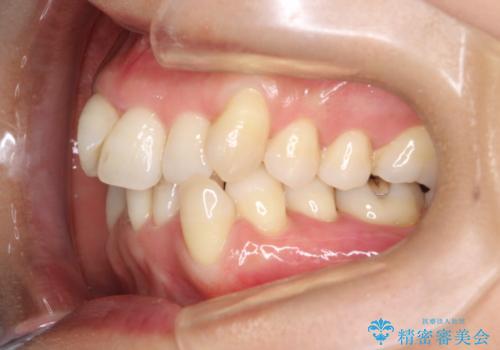

重度のガタガタのインビザラインによる非抜歯矯正

- 上下の歯のガタガタを主訴に来院されました。

インビザラインで奥歯を後方に移動させるのと、歯と歯の間をわずかに削ることでスペースを作り、歯を並べる計画としました。